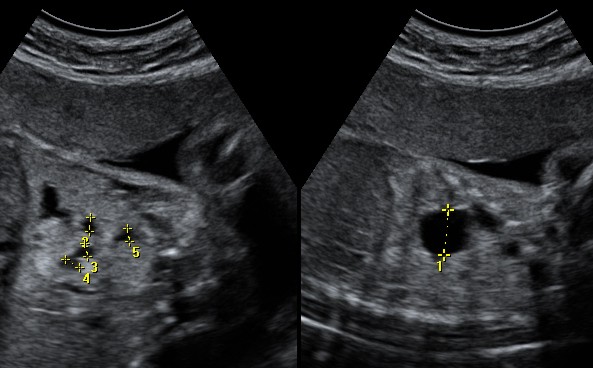

R. � una bambina di 4 anni in cui la diagnosi di malformazione polmonare era stata posta all�et� di 3 anni, come reperto tardivo, secondario a episodi broncopneumonici basali a sinistra. In tale occasione era stata evidenziata per la prima volta lesione microcistica basale sinistra associata ad area enfisematosa perilesionale (Figura 4).

Veniva eseguito l�intervento chirurgico di segmentectomia basale sinistra per via toracoscopia. A 6 mesi dall�intervento era ricomparsa polmonite basale sinistra sulla regione enfisematosa. Il ripetersi di episodi infettivi aveva richiesto, a distanza di due anni dal primo intervento, l�asportazione dell�intero lobo inferiore sinistro.